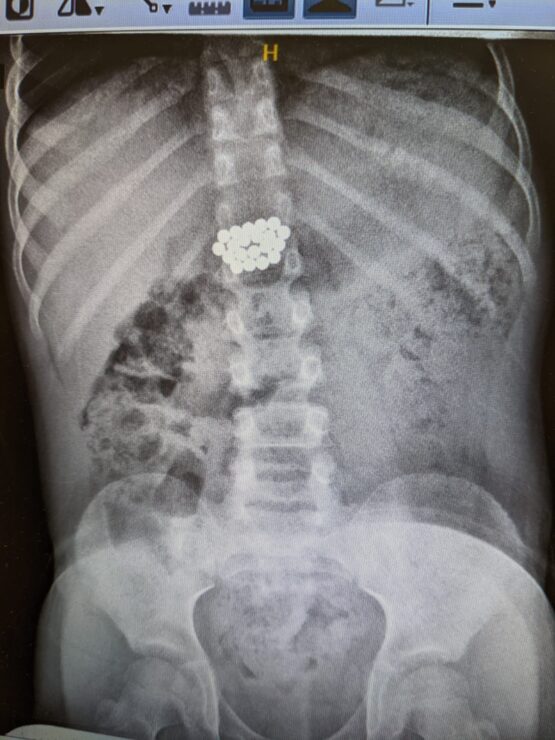

ד"ר אייל זיפמן, מנהל השירות לגסטרואנטרולוגיה ילדים מסביר כי בגלל ההבנה לגבי הנזק שמגנטים עלולים לחולל – והחשש מנקב במעי וזיהום בחלל הבטן, הוחלט לשלוח את הילד באופן מידי לצילום. בצילום נצפו המגנטים במעי הדק במקום שלא ניתן להגיע ללא ניתוח. הוחלט כי נעשה מעקב לבחון את מקומם ובשלב מסוים נמצא כי הם אינם מתקדמים לבד ויש לעשות קולונוסקופיה. המגנטים נמצאו במעי הגס והוצאו בהצלחה".